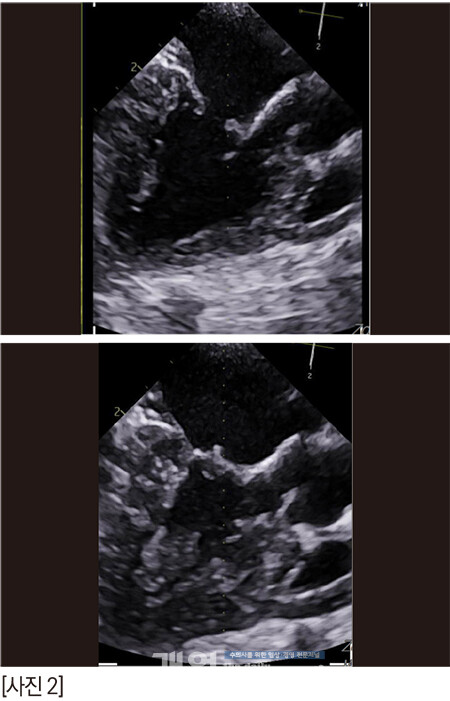

알박사가 ‘risk’라고 하면서 술자들에게 한번 더 주지시킨 이미지이다. 화살표들은 조심해야 하는 부분들 혹은 판막의 심한 퇴행성 변화를 의미하는 곳이다. 이렇게 되면 우리에게는 정답 zone은 딱 하나다.

판막을 가로지르는 저 화살표. 저 곳밖에는 답이 없다. 힘든 수술이 될 것이었다.